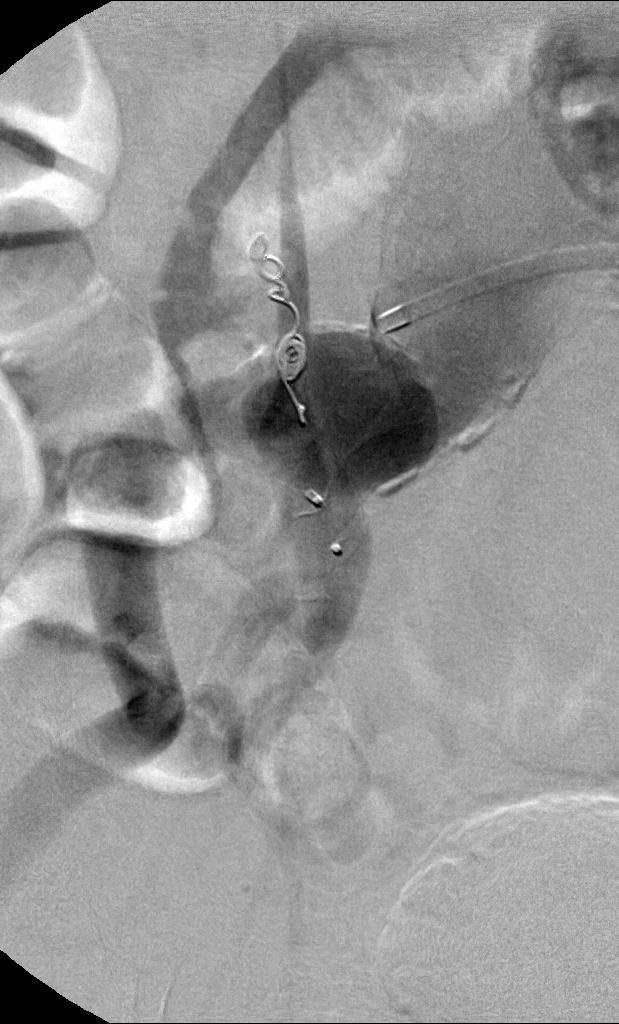

腹主动脉下段和髂动脉瘤,覆膜支撑架置入前,预防II内瘘的栓塞。

脾动脉瘤栓塞